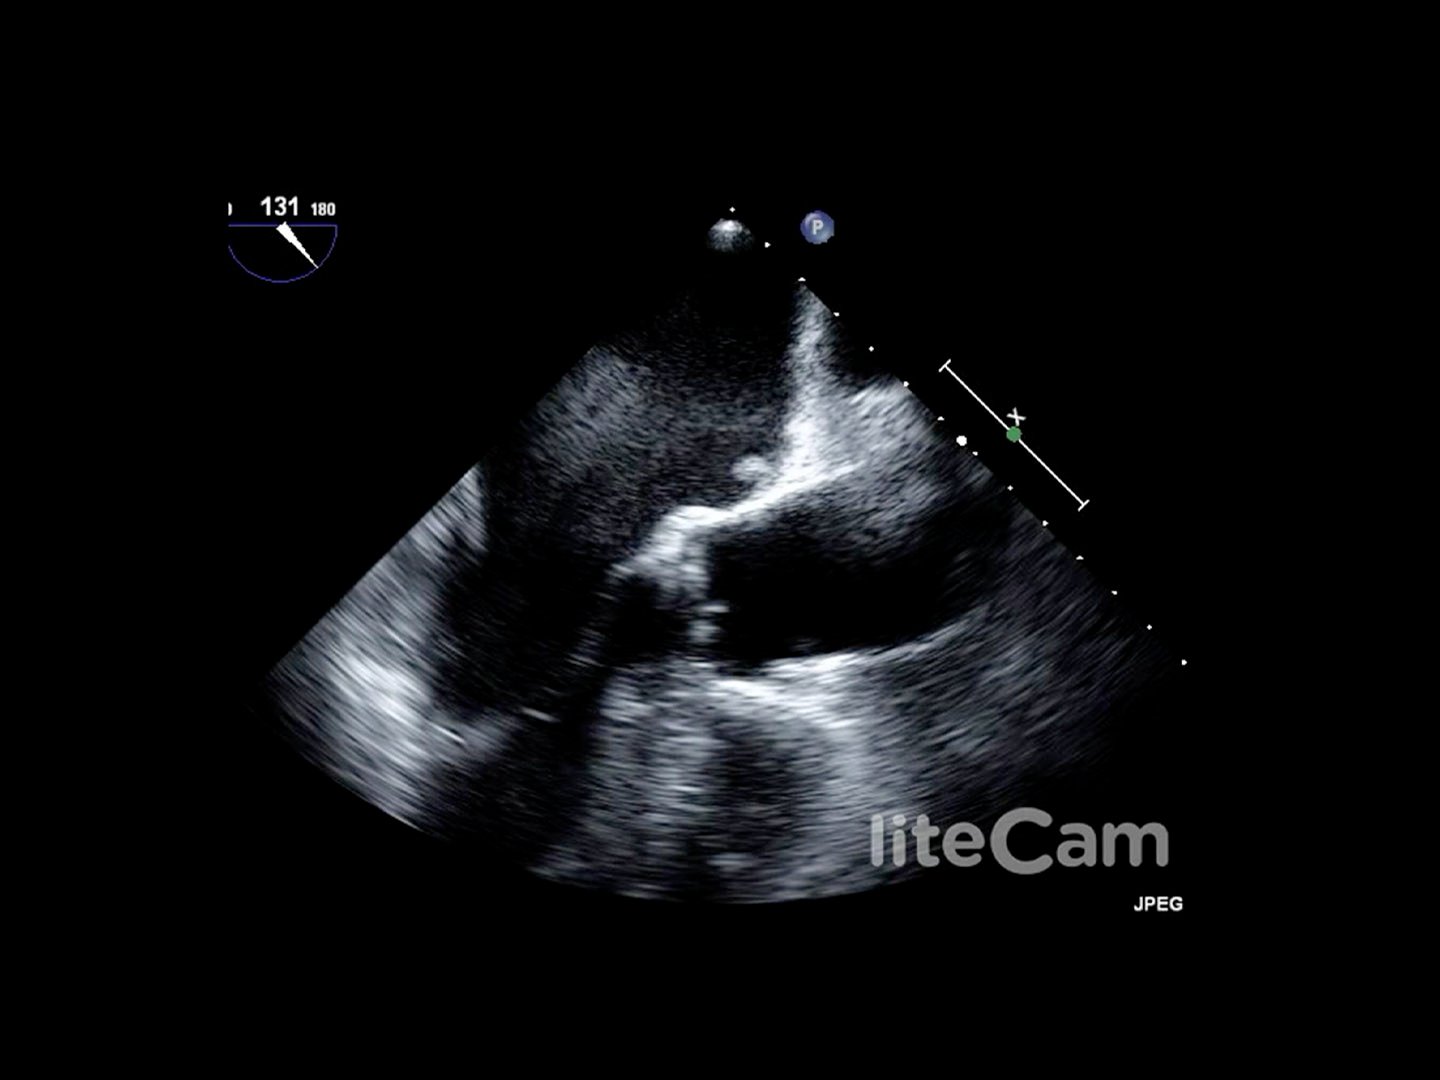

Mobiler Thrombus im linken Vorhof im TEE. Siehe Video

Quelle: CC BY 3.0 "The Supplementary Video shows transesophageal echocardiogram in the midesophageal long axis view. There is significant smoke in the left atrium and a mobile thrombus can be seen in the left atrium.". Wikimedia Commons. User: Shah P, Mithawala P, Konlian D, Soyombo A, Bikkina M.

Prinzipiell kann eine echokardiographische Untersuchung transthorakal erfolgen (TTE) oder transösophageal (TEE). Zum Ausschluss von Thromben z.B. vor einer Kardioversion ist eine TEE Abb. 852 zu empfehlen. Prinzipiell kann ein Thrombus auch im CT mit KM Abb. 853 gesehen werden.

Prinzipiell kann eine echokardiographische Untersuchung transthorakal erfolgen (TTE) oder transösophageal (TEE). Zum Ausschluss von Thromben z.B. vor einer Kardioversion ist eine TEE [[Abb. 8522]] zu empfehlen. Prinzipiell kann ein Thrombus auch im CT mit KM [[Abb. 8533]] gesehen werden.